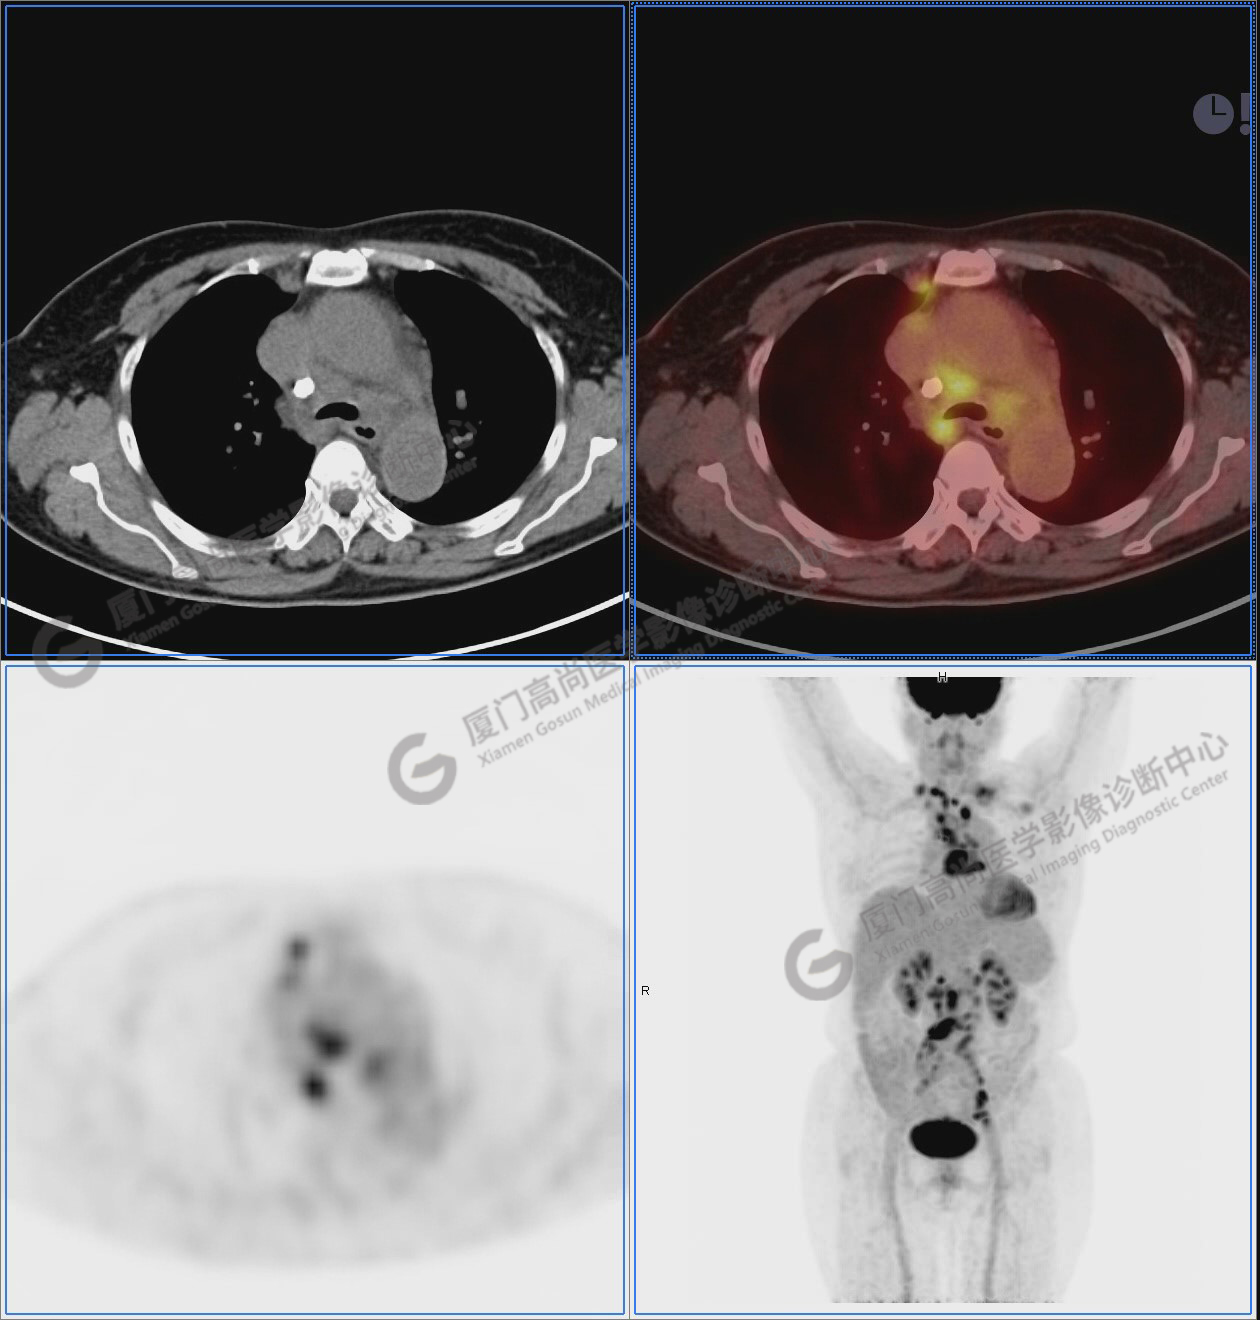

圖1:PET/CT全身圖像

圖2-9:雙側(cè)鎖骨區(qū)、縱隔、右側(cè)內(nèi)乳區(qū)、腸系膜緣、腹膜后、雙側(cè)髂血管旁及盆腔多發(fā)腫大淋巴結(jié)影,代謝不同程度增高,考慮為轉(zhuǎn)移。